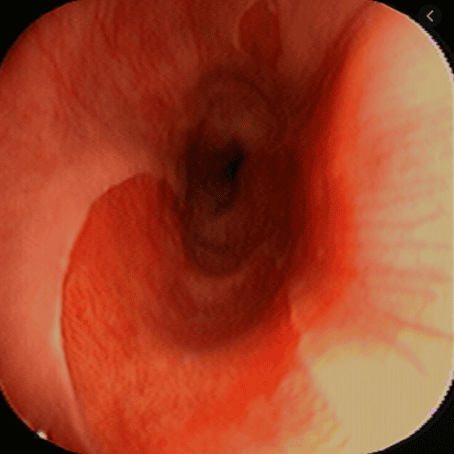

Việc phát hiện các tổn thương giống cấu trúc niêm mạc dạ dày lạc chỗ và xác nhận sau đó bằng mô học sẽ giúp tránh nhầm lẫn giữa ung thư sơ bộ với niêm mạc dị vật. Các cấu trúc niêm mạc dạ dày lạc chỗ xuất hiện với vùng tiêu điểm màu đỏ hoặc hồng cá hồi trên nội soi tiêu chuẩn và là một tổn thương màu nâu sẫm đồng nhất được phân tách rõ ràng với biểu mô vảy màu xanh lục nhạt ở chế độ NBI .

Hình ảnh niêm mạc dạ dày lạc chỗ: Nhiều vùng khu trú nhỏ hình tròn theo hình dạng của mô dạ dày, một trong số chúng hơi nhô lên, được ghi nhận ở trường bên phải, cách cung răng 10cm, ở một thanh niên mắc chứng khó nuốt trên không rõ nguyên nhân.